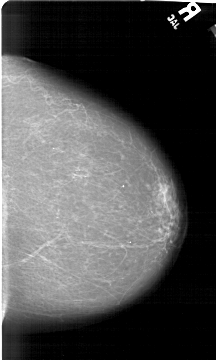

A_1492_1.LEFT_MLO

LEFT_MLO LINES 6181 PIXELS_PER_LINE 4246 BITS_PER_PIXEL 12 RESOLUTION 43.5 OVERLAY

FILE: A_1492_1.LEFT_MLO.OVERLAY

TOTAL_ABNORMALITIES 1

ABNORMALITY 1

LESION_TYPE CALCIFICATION TYPE PUNCTATE DISTRIBUTION CLUSTERED

ASSESSMENT 4

SUBTLETY 3

PATHOLOGY BENIGN

TOTAL_OUTLINES 1

BOUNDARY